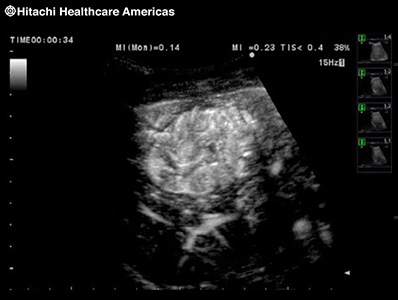

To improve understanding of blood flow information, Fujifilm Healthcare offers harmonics enhanced imaging specifically designed for use with contrast agents. The low MI contrast imaging obtained improves signal-to-noise ratio.

* In the USA, contrast-enhanced ultrasound has not been market cleared by the FDA for all imaging applications.